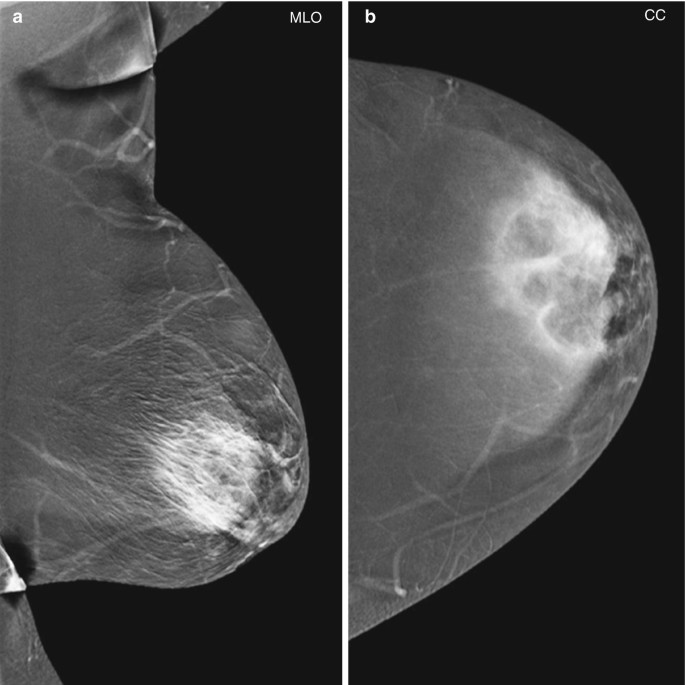

Para diagnosticar correctamente la mastopatía diabética y descartar la posibilidad de cáncer de mama, es necesario realizar una biopsia en la mama. El método más recomendado es la biopsia con una aguja gruesa, que permite extraer una muestra del tejido inflamado para su posterior evaluación en el laboratorio.

Para realizar el diagnóstico adecuado de la mastopatía diabética, es necesario realizar una biopsia en la mama. Este procedimiento consiste en extraer una muestra del tejido inflamado de la mama para su posterior evaluación en el laboratorio. La biopsia con una aguja gruesa es el método más recomendado para obtener el diagnóstico preciso.